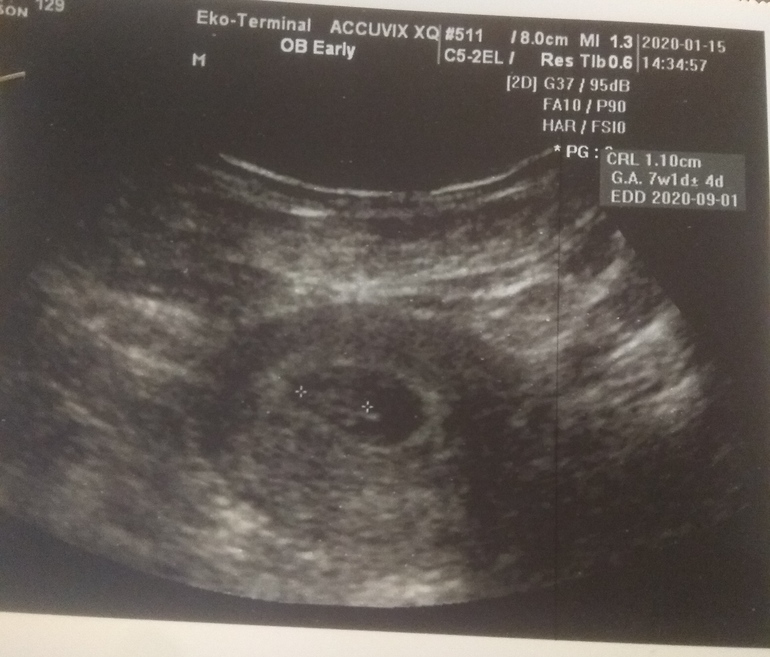

Что??? У автора акушерский срок 8 нед, а эмбриональный (от О) на 2 недели меньше, все правильно она спросила. Просто обычно эмбрион (в дальнейшем плод) до 12 недель догоняет акушерский срок (по М) , а иногда и перегоняет потом. Сейчас пока у вас разница 6 дней, дальше будет скорее всего меньше.

Вы пост читали? У автора была обычная О в середине цикла, причём тут поздняя О вообще? Если О поздняя, отстаёт, если О ранняя -опережает, это дураку понятно, но в большинстве случаев, до 8-9 недель ктр не соответствует сроку по М, немного меньше; потом догоняет. Бывает редко, когда опережает акушерский срок.

Да нормально все.

Интересно только одно: с размеров пя доктор так и не определился? 25-33 мм 🤔